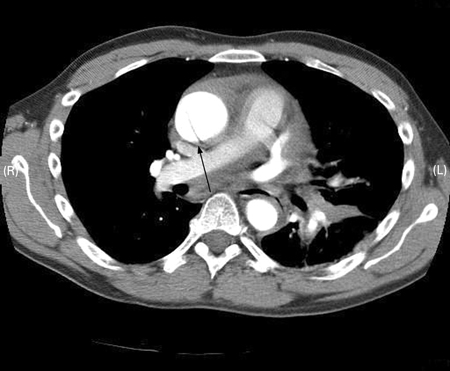

[Figure caption and citation for the preceding image starts]: CT scan showing dissecting aneurysm in a 45-year-old patient with Marfan syndrome experiencing chest pain [Citation ends].

Result

intimal flap in acute and chronic dissection; in chronic dissection the flap may be thickened and there may be evidence of calcification and fewer periaortic reactive changes